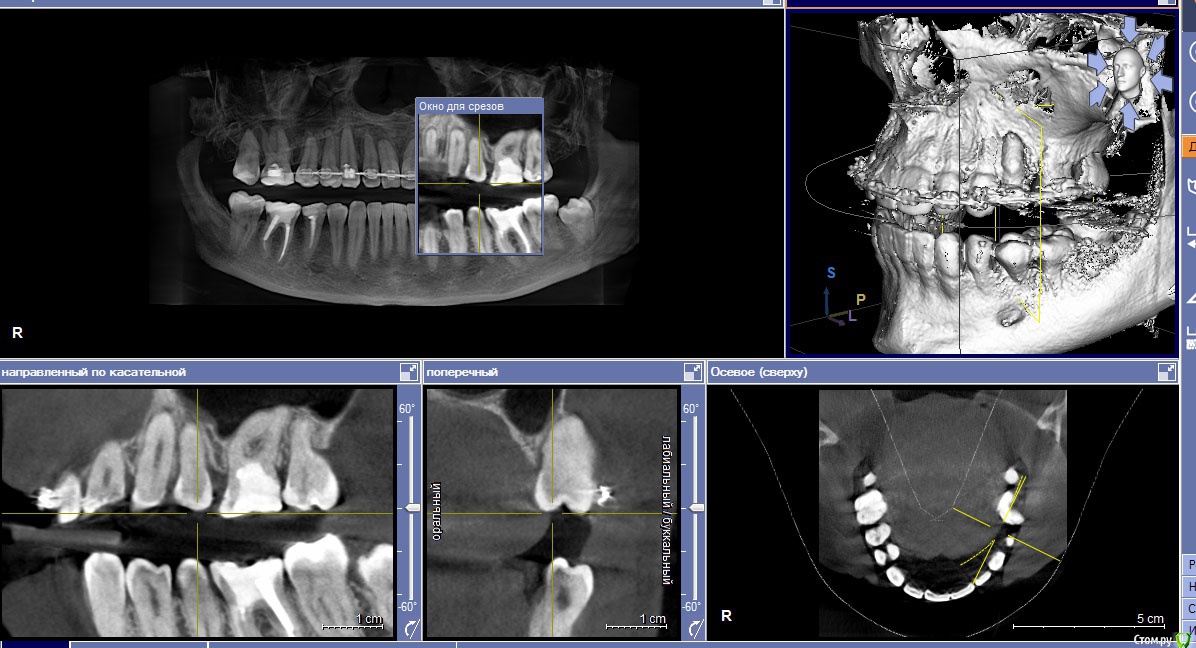

Селенга Опубликовано 14 апреля, 2017 Поделиться Опубликовано 14 апреля, 2017 Добрый день!Подскажите, пожалуйста, что делать в такой ситуации, проходила ортодонтическое лечение, как следствие корень вылез из кости, что в таком случае можно сделать? Этот зуб (см фото - верхний, беспокоит: реагирует на холодное, горячее и жевать практически невозможно) Мне это объяснял лечащий врач так, что костная ткань еще не наросла. Я не думаю, что она может нарасти!Какова вероятность лишиться зуба? Ссылка на комментарий